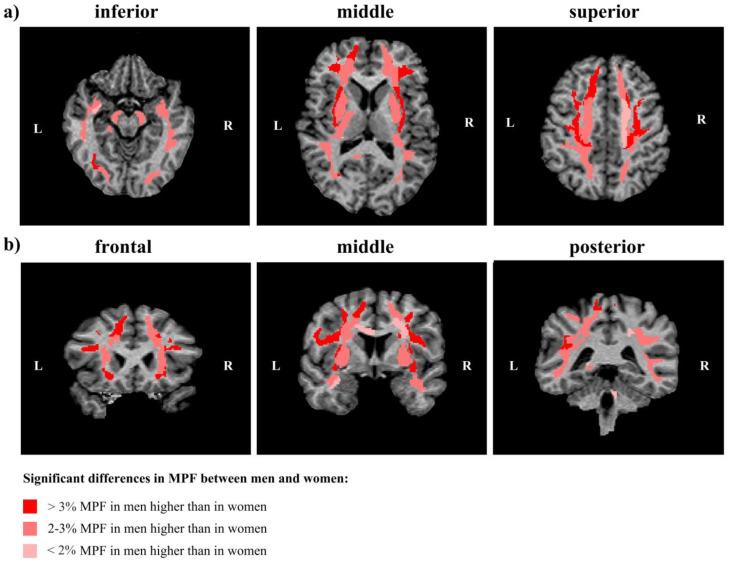

The fundamental question of normal brain myelination in human is still poorly understood. : Age-dependent global, regional, and interhemispheric sex-related differences in brain myelination of 42 (19 men, 23 women) healthy adults (19-67 years) were explored using the MRI method of fast macromolecular fraction (MPF) mapping. : Higher brain myelination in males compared to females was found in global white matter (WM), most WM tracts, juxtacortical WM regions, and putamen. The largest differences between men and women, exceeding 4%, were observed bilaterally in the frontal juxtacortical WM; angular, inferior occipital, and cuneus WM; external capsule; and inferior and superior fronto-orbital fasciculi. The majority of hemispheric differences in MPF were common to men and women. Sex-specific interhemispheric differences were found in juxtacortical WM; men more often had left-sided asymmetry, while women had right-sided asymmetry. Most regions of deep gray matter (GM), juxtacortical WM, and WM tracts (except for projection pathways) showed a later peak age of myelination in women compared to men, with a difference of 3.5 years on average. Body mass index (BMI) was associated with higher MPF and later peak age of myelination independent of age and sex. : MPF mapping showed high sensitivity to assess sex-related differences in normal brain myelination, providing the basis for using this method in clinics.

人类正常脑髓鞘形成的基本问题仍未得到充分理解。使用快速大分子分数(MPF)映射的MRI方法,对42名(19名男性,23名女性)19 - 67岁健康成年人的脑髓鞘形成随年龄变化的整体、区域和半球间性别差异进行了研究。研究发现,男性在整体白质(WM)、大多数WM束、皮质下WM区域和壳核中的脑髓鞘形成高于女性。男性和女性之间最大的差异超过4%,在双侧额叶皮质下WM、角回、枕下回和楔叶WM、外囊以及额眶上束和额眶下束中均有观察到。MPF的大多数半球间差异在男性和女性中是常见的。在皮质下WM中发现了特定性别的半球间差异;男性更常出现左侧不对称,而女性则出现右侧不对称。与男性相比,大多数深部灰质(GM)、皮质下WM和WM束区域(投射通路除外)的髓鞘形成峰值年龄较晚,平均相差3.5岁。体重指数(BMI)与较高的MPF和较晚的髓鞘形成峰值年龄相关,且不受年龄和性别的影响。MPF映射显示出在评估正常脑髓鞘形成的性别差异方面具有很高的敏感性,为该方法在临床上的应用提供了依据。